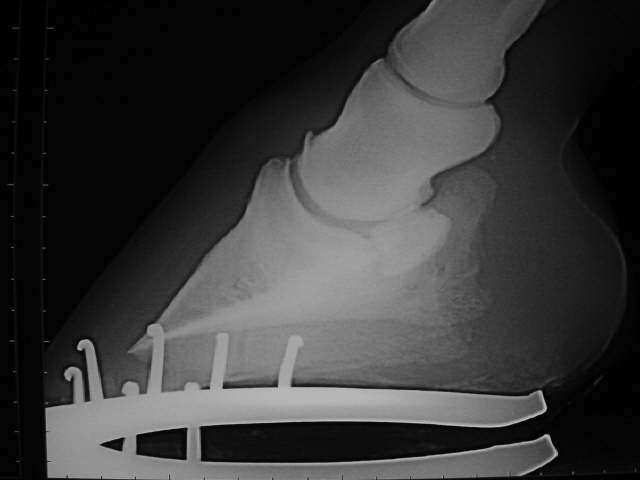

Hufknorpelverknöcherung von der Seite gesehen (Der Flügel, der das Strahlbein überlagert)